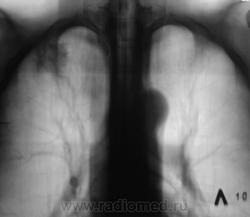

Пациент жалоб не предъявлял, но был «выловлен» после флюорографии, дообследован – 1 серия снимков.

Через 4 месяца пациент закашлял, поднялась температура до 37,5 градусов. Была выполнена рентгенограмма и томограммы – 2 серия снимков.

на представленных последних рентгенотомографических снимках имеется "инфильтративный туберкулез легких". Рекомендовано направить в ПТД для дообследования и лечения. С уважением Nikolas

Фтизиатры согласились с диагнозом инфильтративный туберкулез и пациент был госпитализирован в областную "противотуберкулёзную контору".